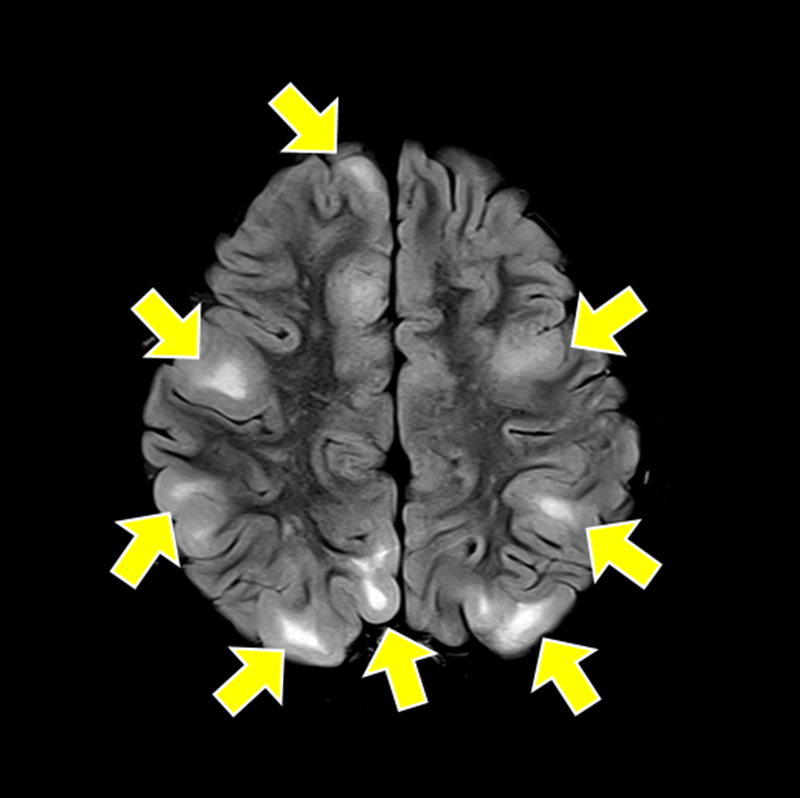

결절 경화증(tuberous sclerosis complex, TSC)은 종양억제유전자의 돌연변이로 인해 세포 증식이 조절되지 않고, 뇌·신장·피부·심장·폐 등 여러 장기에서 양성 종양이 발생하는 유전 희귀질환이다.

가장 흔한 증상인 뇌전증 발작과 피부의 혈관섬유종, 백반증을 비롯해 자폐스펙트럼장애, 인지장애, 신장 낭종, 폐세포 증식증 등 다양한 증상이 연령과 상관없이 나타나기 때문에 조기 진단과 장기적 관리가 필수적이다.